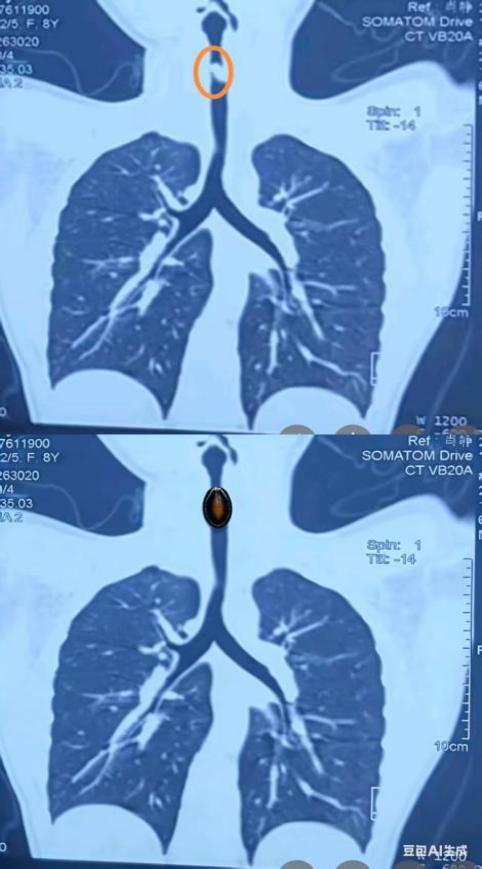

拍片中显示的瓜子位置与AI模拟图 (武汉亚心总医院/供图)

考虑到患儿年龄较小,气道内大部分空间被异物占据,可供呼吸的空间仅剩4-5毫米,若不及时处理,随时可能引发窒息死亡等严重并发症,情况不容乐观,取出这枚气道异物迫在眉睫!医院立即启动急诊绿色通道,在赵剡院长、医务部杜微微主任、护理部徐冬萍主任的统筹协调下,呼吸危重症医学科、麻醉科、重症监护室、儿科、护理团队等多学科专家迅速完成集结,成立儿童气道异物救治小组,为患儿制定了紧急救治方案。

当晚23时整,在呼吸科满宁主任、麻醉科黄维勤主任的带领与护理人员的紧密配合下,手术团队为患儿实施紧急手术,确保患儿在无痛、无动中接受手术。护理团队默契配合,精准传递器械,严密监测生命体征。术中,满主任在患儿气管上段发现一枚约17mm×12mm×2mm的黑色扁平异物(瓜子)紧紧嵌在管腔,周围黏膜因异物刺激而长出少量肉芽组织。

亚总呼吸科满宁主任凭借丰富经验,仅用3分钟便成功将其完整取出,同时针对局部增生的肉芽组织,予以冷冻治疗,有效预防了后续气道狭窄的风险。术后,患儿主气管管腔恢复通畅,生命体征平稳,顺利返回病房。